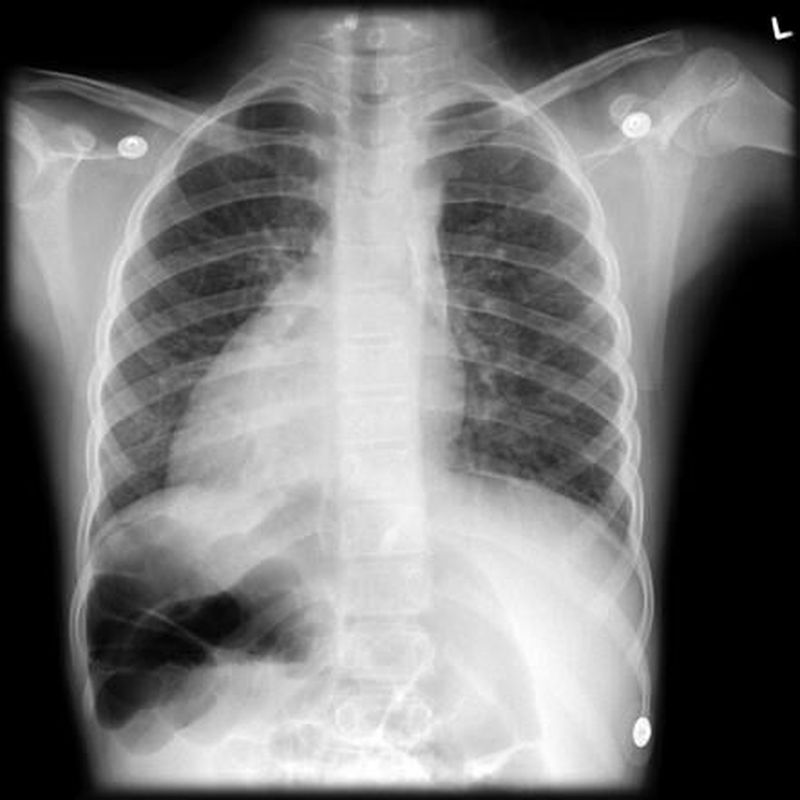

See the x-ray and give me the finding and what's your diagnosis

Dextrocardia

Dextrocardia is a rare heart condition in which the heart points toward the right side of the chest instead of the left side.